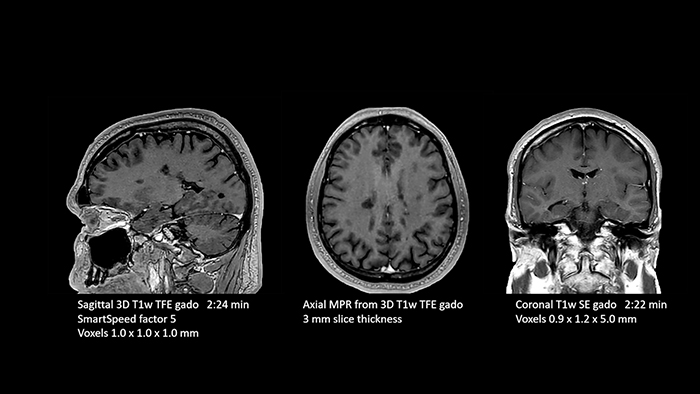

Then, because the computing capacity is so large, we have the images immediately available on the large screen. Higher resolution is very valuable. From the high-resolution 3D sequences, excellent multiplanar reconstruction can be obtained. This makes it easier and faster for us to diagnose and create reports. And while the patient is still lying in the magnet, we can already view the images and make a diagnosis. When the patient comes out, I can immediately ask whether what I see corresponds to the symptoms.”

Dr. Schröter points out that a more confident diagnosis requires high-quality images with more diagnostic information. “Philips SmartSpeed provided that to us. AI denoises the clinical images without losing any important data, resulting in high-resolution images. It keeps all the information we need and makes the images better. We can apply SmartSpeed to almost all sequences. That is a big step forward! We use it for example in 3D imaging and in diffusion-weighted imaging, to dramatically reduce scan time or increase image resolution, which is quite useful. There are small lesions that we would certainly have seen without SmartSpeed, however it would have taken us longer to properly diagnose. In 3D MSK images with extremely high resolution, we uncover the finest anatomical structures and can thus report very detailed findings.”